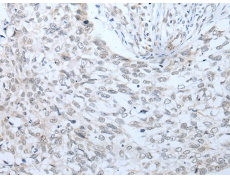

IHC positive control: |

Human lung cancer |

IHC Recommend dilution: |

20-100 |